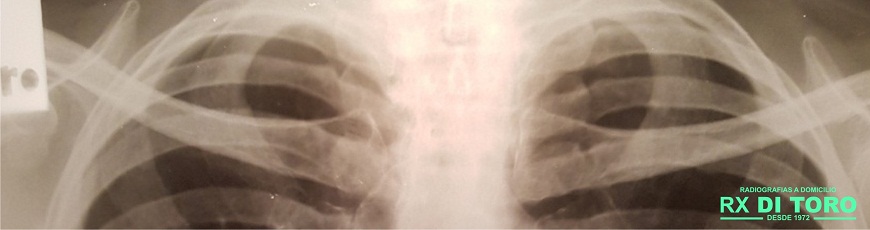

Radiología INFANTÍL

Radiografías para los más pequeños